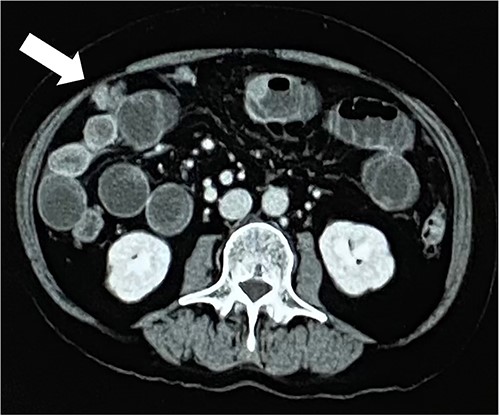

A 79-year-old woman, who had been taking MTX 4.0 mg/week for rheumatoid arthritis since she was 64 years old, came to our hospital complaining of vomiting repeatedly. Physical examination revealed no tenderness in the abdomen, but the abdomen was distended and a mass was observed in the right lower abdomen. Contrast-enhanced computed tomography revealed a mass lesion with contrast effect in the cecum and multiple peritoneal tumors (Figs 1 and 2).